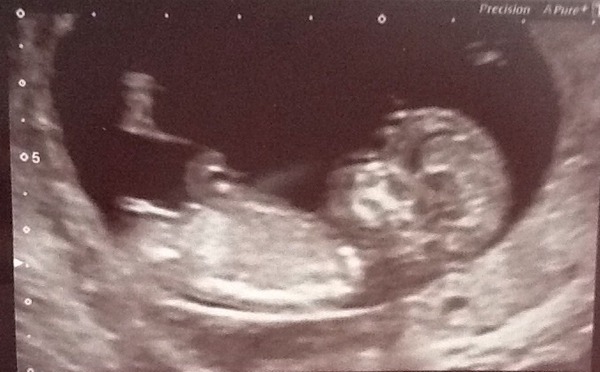

Hello everyone, scan yesterday, am 12+1 due 27th Aoril. I was 1 day out. It was amazing, cried as soon as I saw the little prawn.

Congrats on the scan horseyone! Prawn made me laugh!

And lovely scan Horseyone, my ds1's birthday too!!